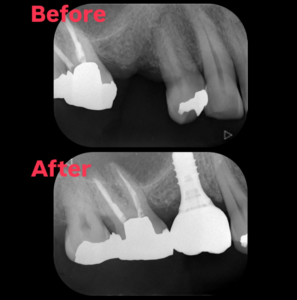

2026.01.04 インプラント インプラント治療行い経過良好です。 インプラント治療を行って3年経過して、良好に機能しております。当院では治療して終了ではなく、術後も経過観察をできる限り行なっていきます。 #松本市歯科医院#松本市歯医者#松本市#歯科#歯医者#歯科医院 #根管治療#歯の矯正#精密根管治療#マイクロスコープ#ラバーダム#インプラント#矯正#マウスピース#小児歯科#親知らず#小児矯正#プレオルソ#セラミック#ジルコニア#顎関節#嚥下